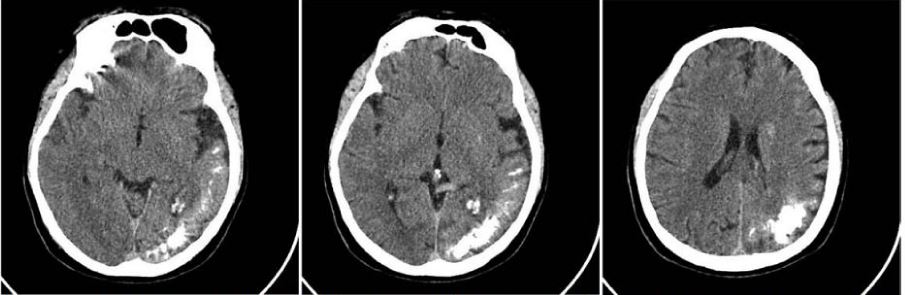

Магнитно-резонансная (МРТ) или компьютерная томография (КТ)

1. Уменьшение размеров пораженного полушария коры головного мозга.

2. Обнаружение большого количества кальцинированных включений в ткань мозга – симптом «железнодорожных путей», называемый так из-за параллельного расположения кальцифицированных участков.

3. Увеличение пространств, по которым течет ликвор, в том числе полостей головного мозга – желудочков.

image

Мультиспиральная компьютерная томография